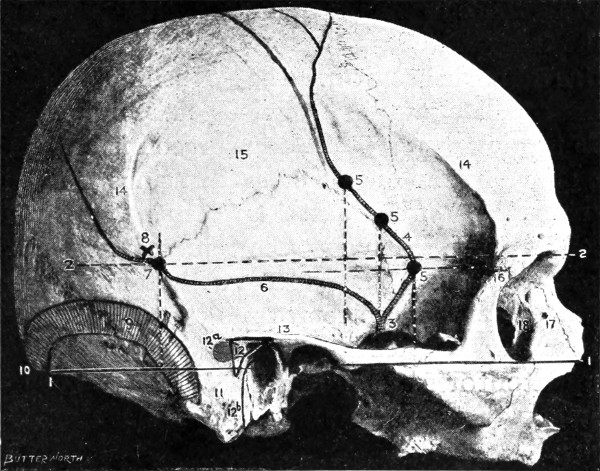

Fig. 2. Cranio-cerebral Topography. 1, 1, Reid’s base-line; 2, 2, A line parallel to the above at the level of the supra-orbital margin; 3, The middle meningeal artery; 4, The anterior branch; 5, 5, 5, The three sites for trephining; 6, The posterior branch; 7, The site for trephining; 8, The point for trephining to reach the descending horn of the lateral ventricle; 9, The lateral sinus; 10, The inion; 11, The mastoid process; 12, Macewen’s suprameatal triangle; 12a, The mastoid antrum; 12b, The facial nerve; 13, The suprameatal and supramastoid crests; 14, 14, The temporal crest; 15, The temporal fossa; 16, The external angular frontal process; 17, The tendo-oculi attachment; 18, The lachrymal groove. (Reproduced, by the permission of Mr. H. K. Lewis, from the author’s work on ‘Landmarks and Surface-markings’.)